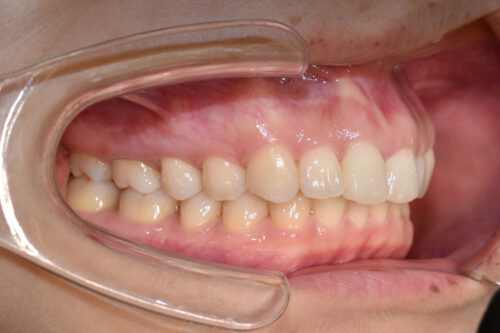

初診時年齢 30歳 女性

過蓋咬合と

叢生(歯ならびの デコボコ)

を主訴に

池袋よりひとつ隣駅の東京都豊島区大塚駅すぐの大塚たまみ矯正歯科へ

いらっしゃいました。

下の歯が 全く見えない状態で

上下の歯が 翼のように ガタついて(翼状捻転)いる

状態でした。

ワイヤー矯正治療10か月後です。